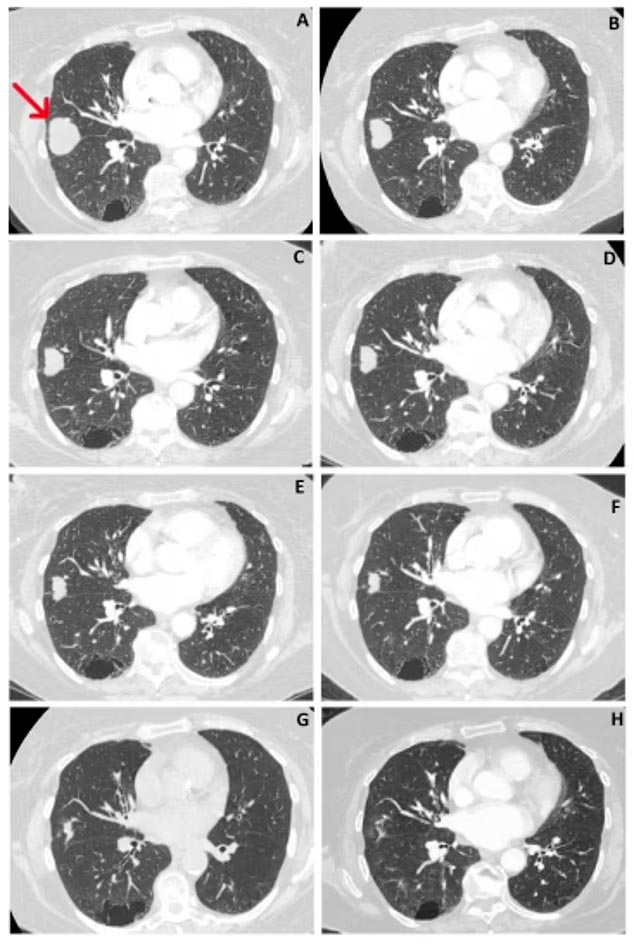

La tumeur initiale de 41 mm en juin 2018 a été réduite à 10 mm en février 2021, reflétant une réduction globale de 76 % de la taille. Le cas a été porté à l’attention de l’équipe hospitalière de la patiente en février 2019 lorsqu’une IRM a montré une réduction de la taille de la tumeur, alors qu’elle n’avait reçu aucun traitement conventionnel pour son cancer du poumon.